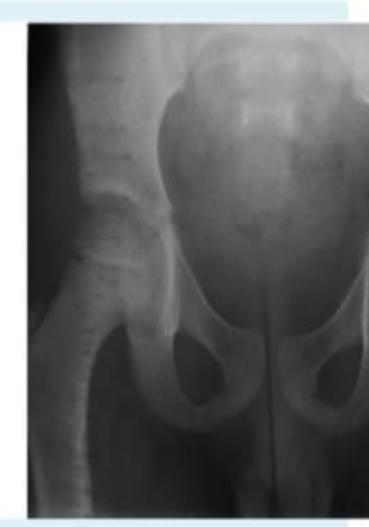

A 15-month-old child was brought to the clinic because of painless limping. There is no history of trauma. The pelvic x-ray is shown.

Q1: Write two abnormalities seen on the X-ray.

- Lateralization of the ossifying centre

- Acetabular angle more than 27ยฐ

- Broken Shenton line

- Shortening of the line from greater trochanter to the horizontal line

Q2: What is the most probable diagnosis?

- Developmental dysplasia of the hip (DDH)